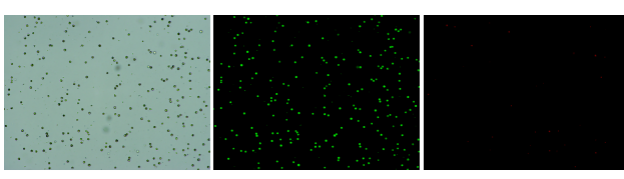

發(fā)表日期:2021年1月

樣本設(shè)計:12例原發(fā)肝癌和6例早期復(fù)發(fā)肝癌患者的腫瘤組織和癌旁組織,進(jìn)行全長單細(xì)胞轉(zhuǎn)錄組測序,并采用2個獨(dú)立的隊列(第1隊列,4例患者的配對原發(fā)腫瘤和復(fù)發(fā)腫瘤;第2隊列,47例患者的配對原發(fā)腫瘤和復(fù)發(fā)腫瘤)對相關(guān)結(jié)果進(jìn)行驗證(見下圖)。

研究內(nèi)容:本文構(gòu)建了12例原發(fā)性肝細(xì)胞癌患者和6例早期復(fù)發(fā)肝細(xì)胞癌患者癌和癌旁的單細(xì)胞圖譜,發(fā)現(xiàn)與原發(fā)性肝癌微環(huán)境相比,復(fù)發(fā)性肝癌呈現(xiàn)獨(dú)特的免疫生態(tài)系統(tǒng),即DC比例增加,Tregs減少,T細(xì)胞增殖減少,CD8+T細(xì)胞豐度更高。通過整合TCR克隆和Monocle分析,研究者確定了CD8+T細(xì)胞的分化路徑。PT和RT樣本中CD8+T細(xì)胞表現(xiàn)出相同的分化軌跡,但表現(xiàn)出明顯不同的免疫和轉(zhuǎn)錄狀態(tài),與原發(fā)性肝癌樣本(PT)相比,早期復(fù)發(fā)性肝癌樣本(RT)中的CD8+T細(xì)胞耗竭信號的表達(dá)減少,表達(dá)免疫檢查點(diǎn)基因的細(xì)胞比例減少,組織駐留基因增加,而共刺激和耗竭分子減少。同時,研究者發(fā)現(xiàn)免疫檢查點(diǎn)基因CTLA4、HAVCR2和TIGIT在復(fù)發(fā)腫瘤的T細(xì)胞中表達(dá)降低,這表明針對這些標(biāo)志物的檢查點(diǎn)阻斷方法可能對原發(fā)性肝癌有效,但對復(fù)發(fā)患者無效。綜上所述,治療原發(fā)性或復(fù)發(fā)性肝癌需要不同的治療方法。

人肝癌樣本,懸液背景干凈,活性91.69%,結(jié)團(tuán)率6%

人膽管癌樣本,活性90.45%,結(jié)團(tuán)率7.2%

Tips: 肝實(shí)質(zhì)細(xì)胞經(jīng)過解離后因為缺氧非常容易發(fā)生凋亡,導(dǎo)致占比很低,如果老師關(guān)注肝實(shí)質(zhì)細(xì)胞的話,建議采用單細(xì)胞核懸液的方法。